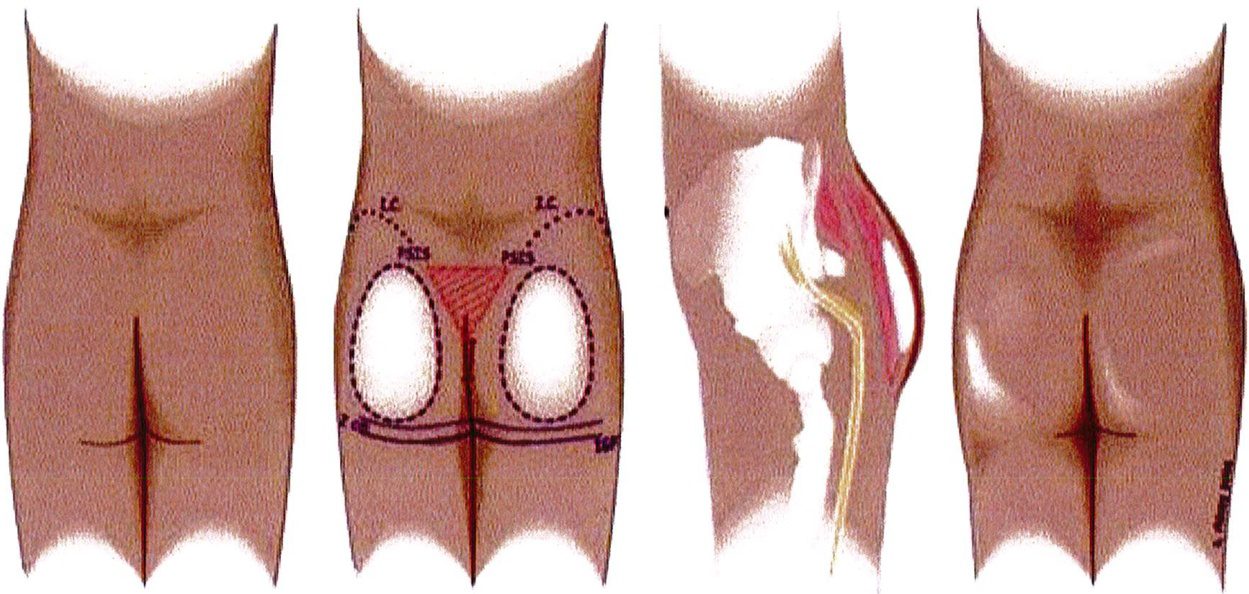

của chúng. Cân cơ mông lớn – nhõ đều đi cùng với chiều hướng của lớp cơ chúng che phủ. Nên nhớ hệ thống cân cơ này buộc phải bảo tồn tối đa trong bất kỳ phẫu thuật nâng mông thẩm mỹ nào. Và khối implant khi đặt ở vị trí dưới cân sẽ đảm bảo không ảnh hưởng tới bất kỳ cấu trúc mạch máu thần kinh sâu nào (Hình 3).

liên quan tới mặt phẳng implant, việc tìm ra một mặt phẳng khác có thể implant để hạn chế tối đa những thiếu sót của các ký thuật khác là điều cần thiết. Và mặt phẳng dưới ra đời (Hình 1). Kỹ thuật này được phát triển dựa trên nhiều nghiên cứu trên các tử thi nhằm phân tích các lớp giải phẫu riêng biệt. Cân vùng mông bám rất chắc ở cả nguyên ủy và bám tận của nó. Chúng bao phủ cơ mông lớn, là cấu trúc lớn nhất và nông nhất ở vùng mông, đóng vai trò quan trọng trong việc tạo nên hình dáng của mông.

Hình. 1. Tương quan giải phẫu và vị trí của khối implant dưới cân cho thấy, chúng phải nằmở vị trí trung tâm của mông và được che phủ hoàn toàn bởi hệ thống cân mạc bao phủ cơ. Dây thần kinh hông to, có thể nhìn thấy rõ từ phía bên, cách túi implant một khoảng cách tương đối an toàn. (Trích từ de la Peda JA. Subfascial technique for Gluteal Augmentation. Aesthet Surg J 2004;24:265-73; đã xin phép trước khi đăng tải.)